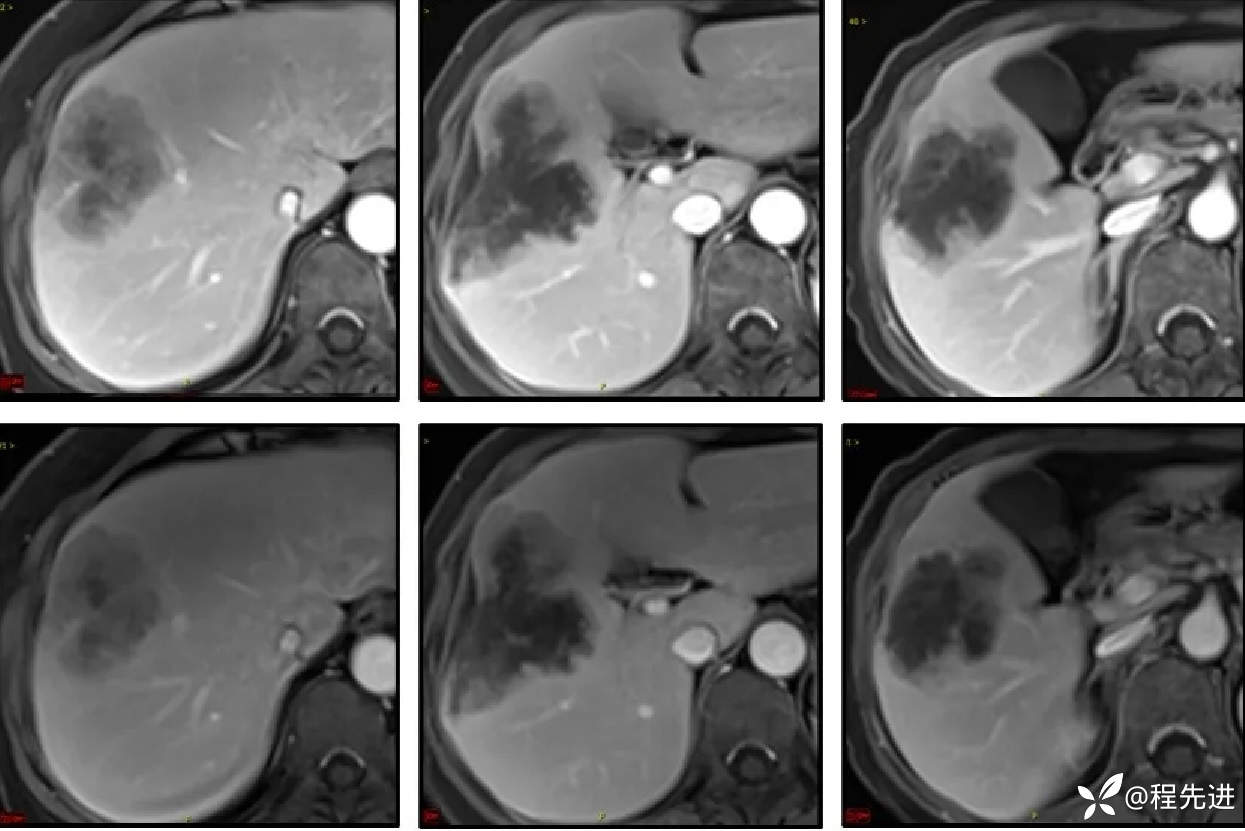

移行期、肝胆期: